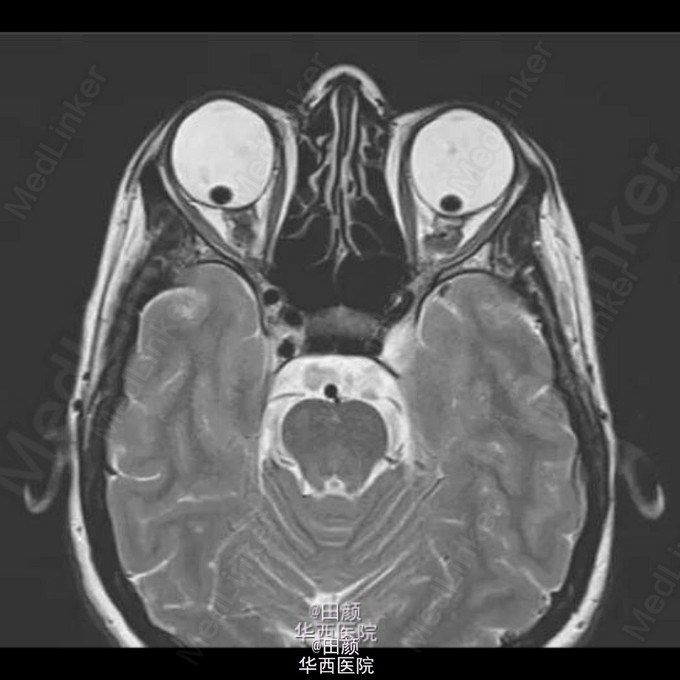

晶状体异位

患者女,31岁,出现双眼视力渐进性下降3月,轻度感音神经性耳聋2周,马凡综合征病史。眼科检查:双眼视力OD:0.25,OS:0.05,双眼眼压正常,散瞳后裂隙灯检查检查发现双眼晶状体脱位入玻璃体腔,眼底检查发现存在视网膜变性,但未见视网膜撕裂及视网膜脱离的迹象。由于患者出现无法解释的听力下降而予以头颅MRI扫描,检查结果如下。